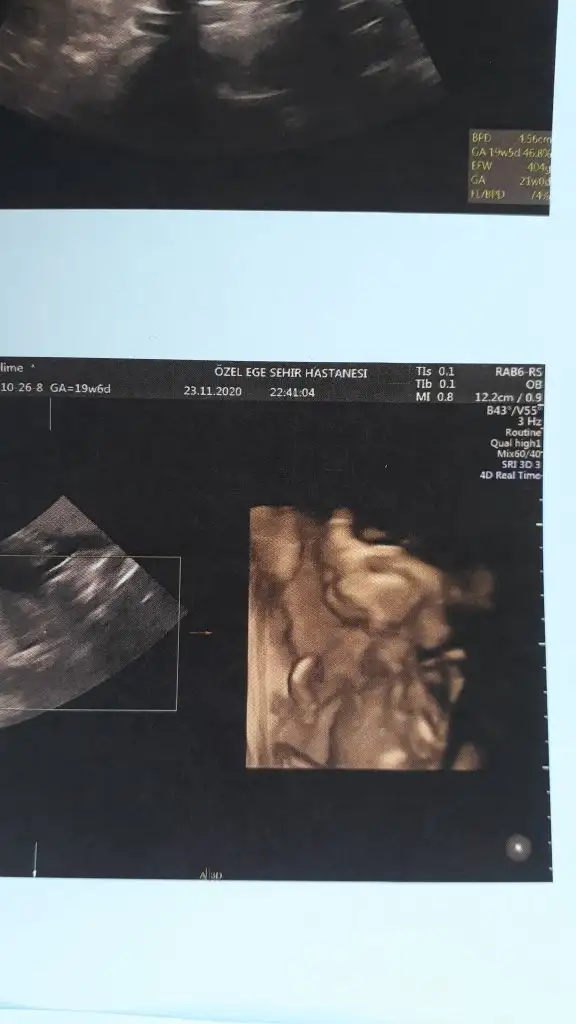

Genelde meyve suyu ya da çikolata diyorlar .. Ayrıntılı güzel geçer inşallah..Kızlar yarın ayrıntılı ultrasonum var. Her kontrole gittiğimizde ya ters duruyor, ya da pozisyonunu hiç değiştirmiyor. Bebeği hareketlendirmek için neler yemek içmek lazım?

Benim gideceğim doktorun sekreteri ultrasona girmeden yarım saat önce tatlı bir şeyler yiyebilirsin dedi. Ama benim kız genelde kahvaltıdan sonra hareketleniyorKızlar yarın ayrıntılı ultrasonum var. Her kontrole gittiğimizde ya ters duruyor, ya da pozisyonunu hiç değiştirmiyor. Bebeği hareketlendirmek için neler yemek içmek lazım?

Benimkinde hep secdedeydi sıfır hareket bu sefer giderken bir muz yedim bir palet çikolata ve filtre kahve yürüyüş ayrıntılıya bir girdik doktor bebeğimi durduramadıKızlar yarın ayrıntılı ultrasonum var. Her kontrole gittiğimizde ya ters duruyor, ya da pozisyonunu hiç değiştirmiyor. Bebeği hareketlendirmek için neler yemek içmek lazım?